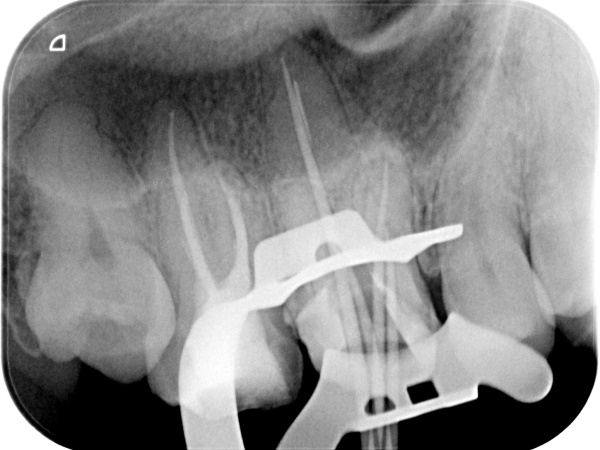

根管治療中(試適時)